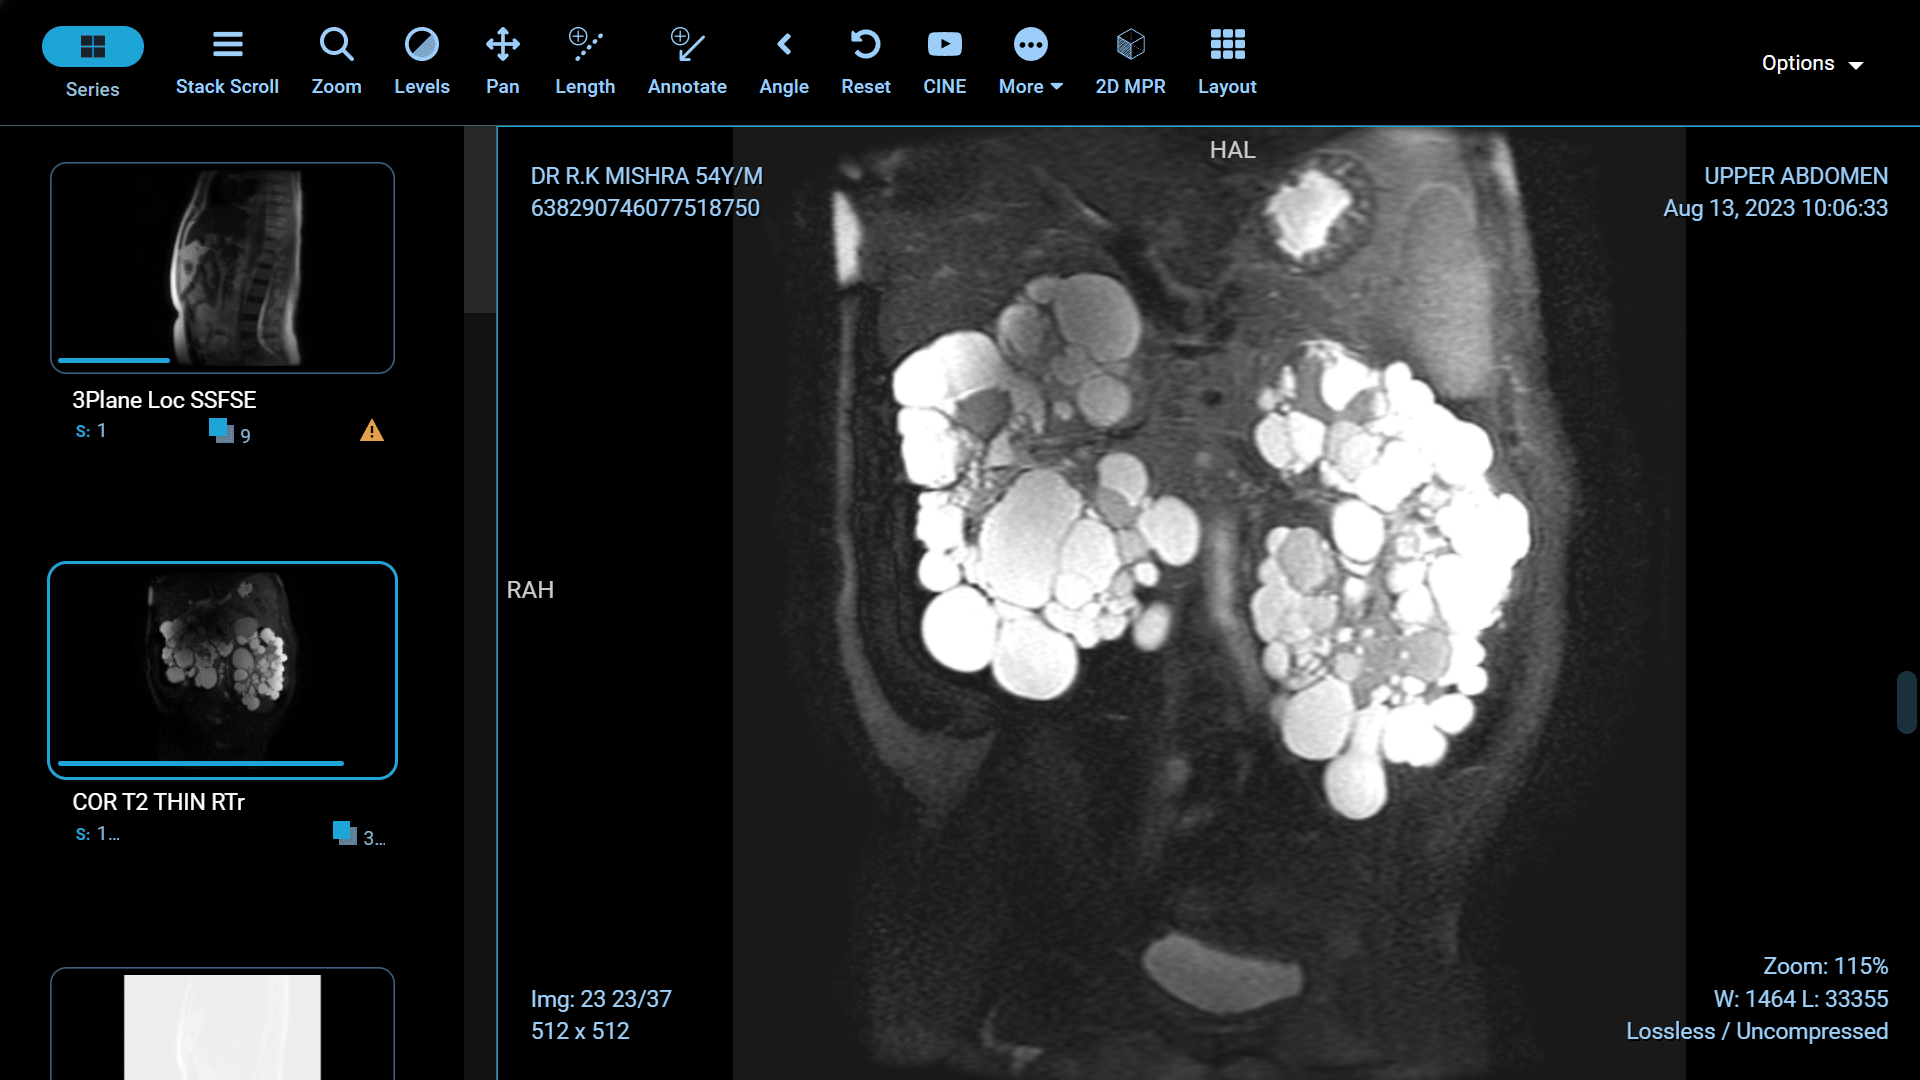

Polycystic Kidney Disease (PKD) is a genetic disorder characterized by the formation of fluid-filled cysts in the kidneys, which can lead to renal failure if left untreated. Fortunately, recent advancements in medical science have paved the way for more effective treatments and improved the quality of life for those affected by this condition. In this article, we will explore some of the groundbreaking innovations in PKD treatment.

Surgical intervention is often required in advanced cases of PKD, and recent innovations in surgical techniques have made these procedures less invasive and more effective. Laparoscopic and robotic-assisted surgeries allow for smaller incisions, reduced pain, shorter hospital stays, and quicker recovery times. These advancements have significantly improved the overall experience for PKD patients undergoing surgery.

Foam sclerotherapy is a medical procedure that involves injecting a specialized foam directly into kidney cysts. The foam is made by mixing a liquid sclerosing agent, typically a solution of alcohol or polidocanol, with air or gas to create a stable, persistent foam. This foam is then injected into the cyst through a thin needle under ultrasound or CT guidance.

The success of foam sclerotherapy lies in its ability to cause intentional injury to the cyst lining, promoting inflammation and scarring. This process leads to the collapse and sealing of the cyst, preventing further fluid accumulation and reducing the cyst's size.

Pain Reduction: Many patients experience relief from pain and discomfort associated with kidney cysts after foam sclerotherapy.